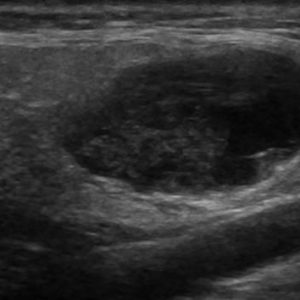

U tuyến nước bọt

Lượt xem: 150» 18-01-2021 -

U tuyến nước bọt

Lượt xem: 775» 18-01-2021 -

U tuyến nước bọt

Lượt xem: 164» 18-01-2021 -